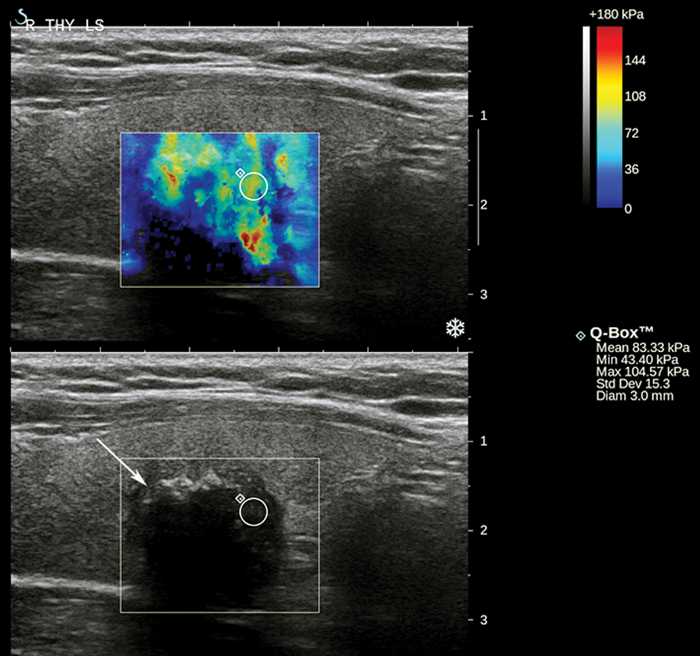

Since 2005, over 50 pilot studies of strain elastography and a handful of shear wave elastography studies have evaluated the accuracy of USE for thyroid malignancy [2, 4-10]. These have differed considerably in terms of sample size (mean ~100 nodules, range 16-912), patient and nodule inclusion / exclusion criteria, USE technology, practical technique, nodule scoring system and reference standards used. Approximately 90% of malignancies in these studies are papillary thyroid carcinomas, thus published accuracy results probably pertain to this malignant histology. Encouragingly, most studies document strain and shear wave indices equating to higher stiffness in malignant compared to benign nodules (Figures 1-2). For strain elastography, a recent meta-analysis of 5481 thyroid nodules from 31 studies calculated a pooled 79% sensitivity and 77% specificity for malignancy using qualitative assessment, and 85% sensitivity and 80% specificity using strain ratios [4]. Promising results are also emerging for shear wave elastography [6, 9]. For example, in a study of 297 nodules, Veyrieres et al. found a cut off of >66kPa achieved 80% sensitivity and 90.5% specificity for malignancy [9]. Importantly, combining USE with grayscale US features achieved 97% sensitivity and 99.5% negative predictive value.

Figure 2: Grayscale US image with corresponding shear wave elastogram of a hypoechoic nodule (arrow) containing focal calcifications with distal acoustic shadowing, histologically confirmed as papillary thyroid carcinoma. The elastogram colour scale ranges from blue to red (0 to 180 kPa). The nodule displays heterogeneous high stiffness hues. The small region of interest has a maximum stiffness of 105 kPa, which is relatively stiff according to the optimal cut-off of 66 kPa for malignancy in a pilot study by Veyrieres et al [9].